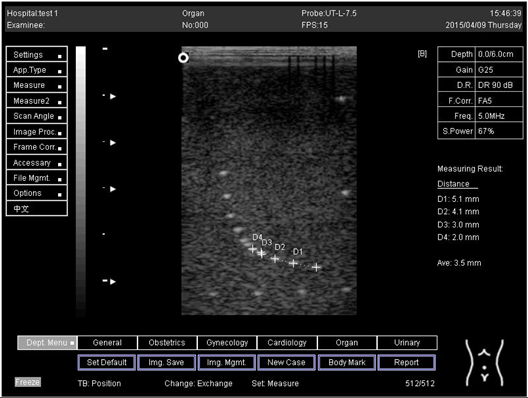

Lateral resolution

Biomimetics 07 00130 i002

D1 = 5.0

D2 = 4.0

D3 = 3.0

D4 = 2.2